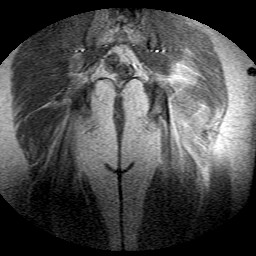

Esami: RMN BACINO

Evidenti e simmetriche alterazioni osteofitosiche in regione coxo femorale con riduzione delle rime articolari. Degenerazione completa del cercine glenoideo. Non attuali segni di versamento articolare. Non segni di edema osseo che escludono attuale algodistrofia od osteonecrosi. Lieve e simmetrica riduzione del trofismo della muscolatura glutea.